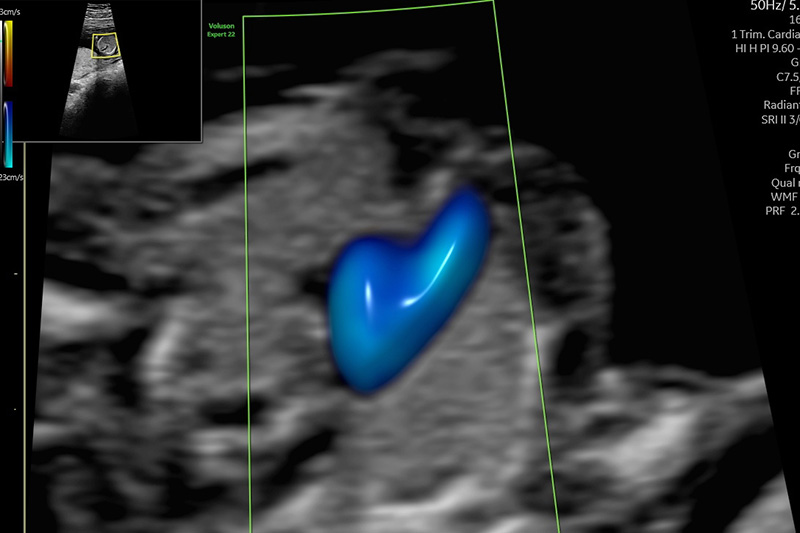

Bei der Untersuchung erfolgt eine Überprüfung des Entwicklungszustandes des Embryos und eine erste Organuntersuchung, soweit es die Verhältnisse des frühen Schwangerschaftsalters zulassen. Zahlreiche Fehlbildungen sind zu diesem Zeitpunkt bereits erkennbar, jedoch sind einige Organe (z.B. Herz, Wirbelsäule) zu diesem Zeitpunkt noch nicht abschließend beurteilbar. Eine abschließende Organbeurteilung kann erst zu einem späteren Zeitpunkt, üblicherweise in der ca. 20./22.SSW, beispielsweise über den weiterführenden Organultraschall (Feindiagnostik) erfolgen.